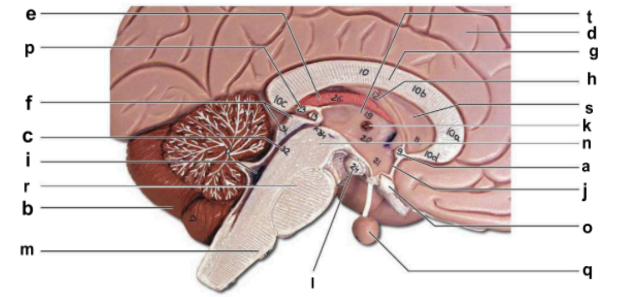

Identify the structure labeled “a” in the image.

anterior commissure

Identify the structure labeled “b” in the image.

cerebellum

Identify the structure labeled “c” in the image.

cerebral aqueduct

Identify the structure labeled “d” in the image.

cerebral hemisphere

Identify the structure labeled “e” in the image.

choroid plexus

Identify the structure labeled “f” in the image.

corpora quadrigemina

Identify the structure labeled “g” in the image.

corpos callosum

Identify the structure labeled “h” in the image.

fornix

Identify the structure labeled “i” in the image.

fourth ventricle

Identify the structure labeled “j” in the image.

hypothalamus

Identify the structure labeled “k” in the image.

interthalamic adhesion

Identify the structure labeled “l” in the image.

mammilary body

Identify the structure labeled “m” in the image.

medulla oblongata

Identify the structure labeled “n” in the image.

midbrain

Identify the structure labeled “o” in the image.

optic chiasma

Identify the structure labeled “p” in the image.

pineal gland

Identify the structure labeled “q” in the image.

pituitary gland

Identify the structure labeled “r” in the image.

pons

Identify the structure labeled “s” in the image.

septum pellucidum

Identify the structure labeled “t” in the image.

thalamus